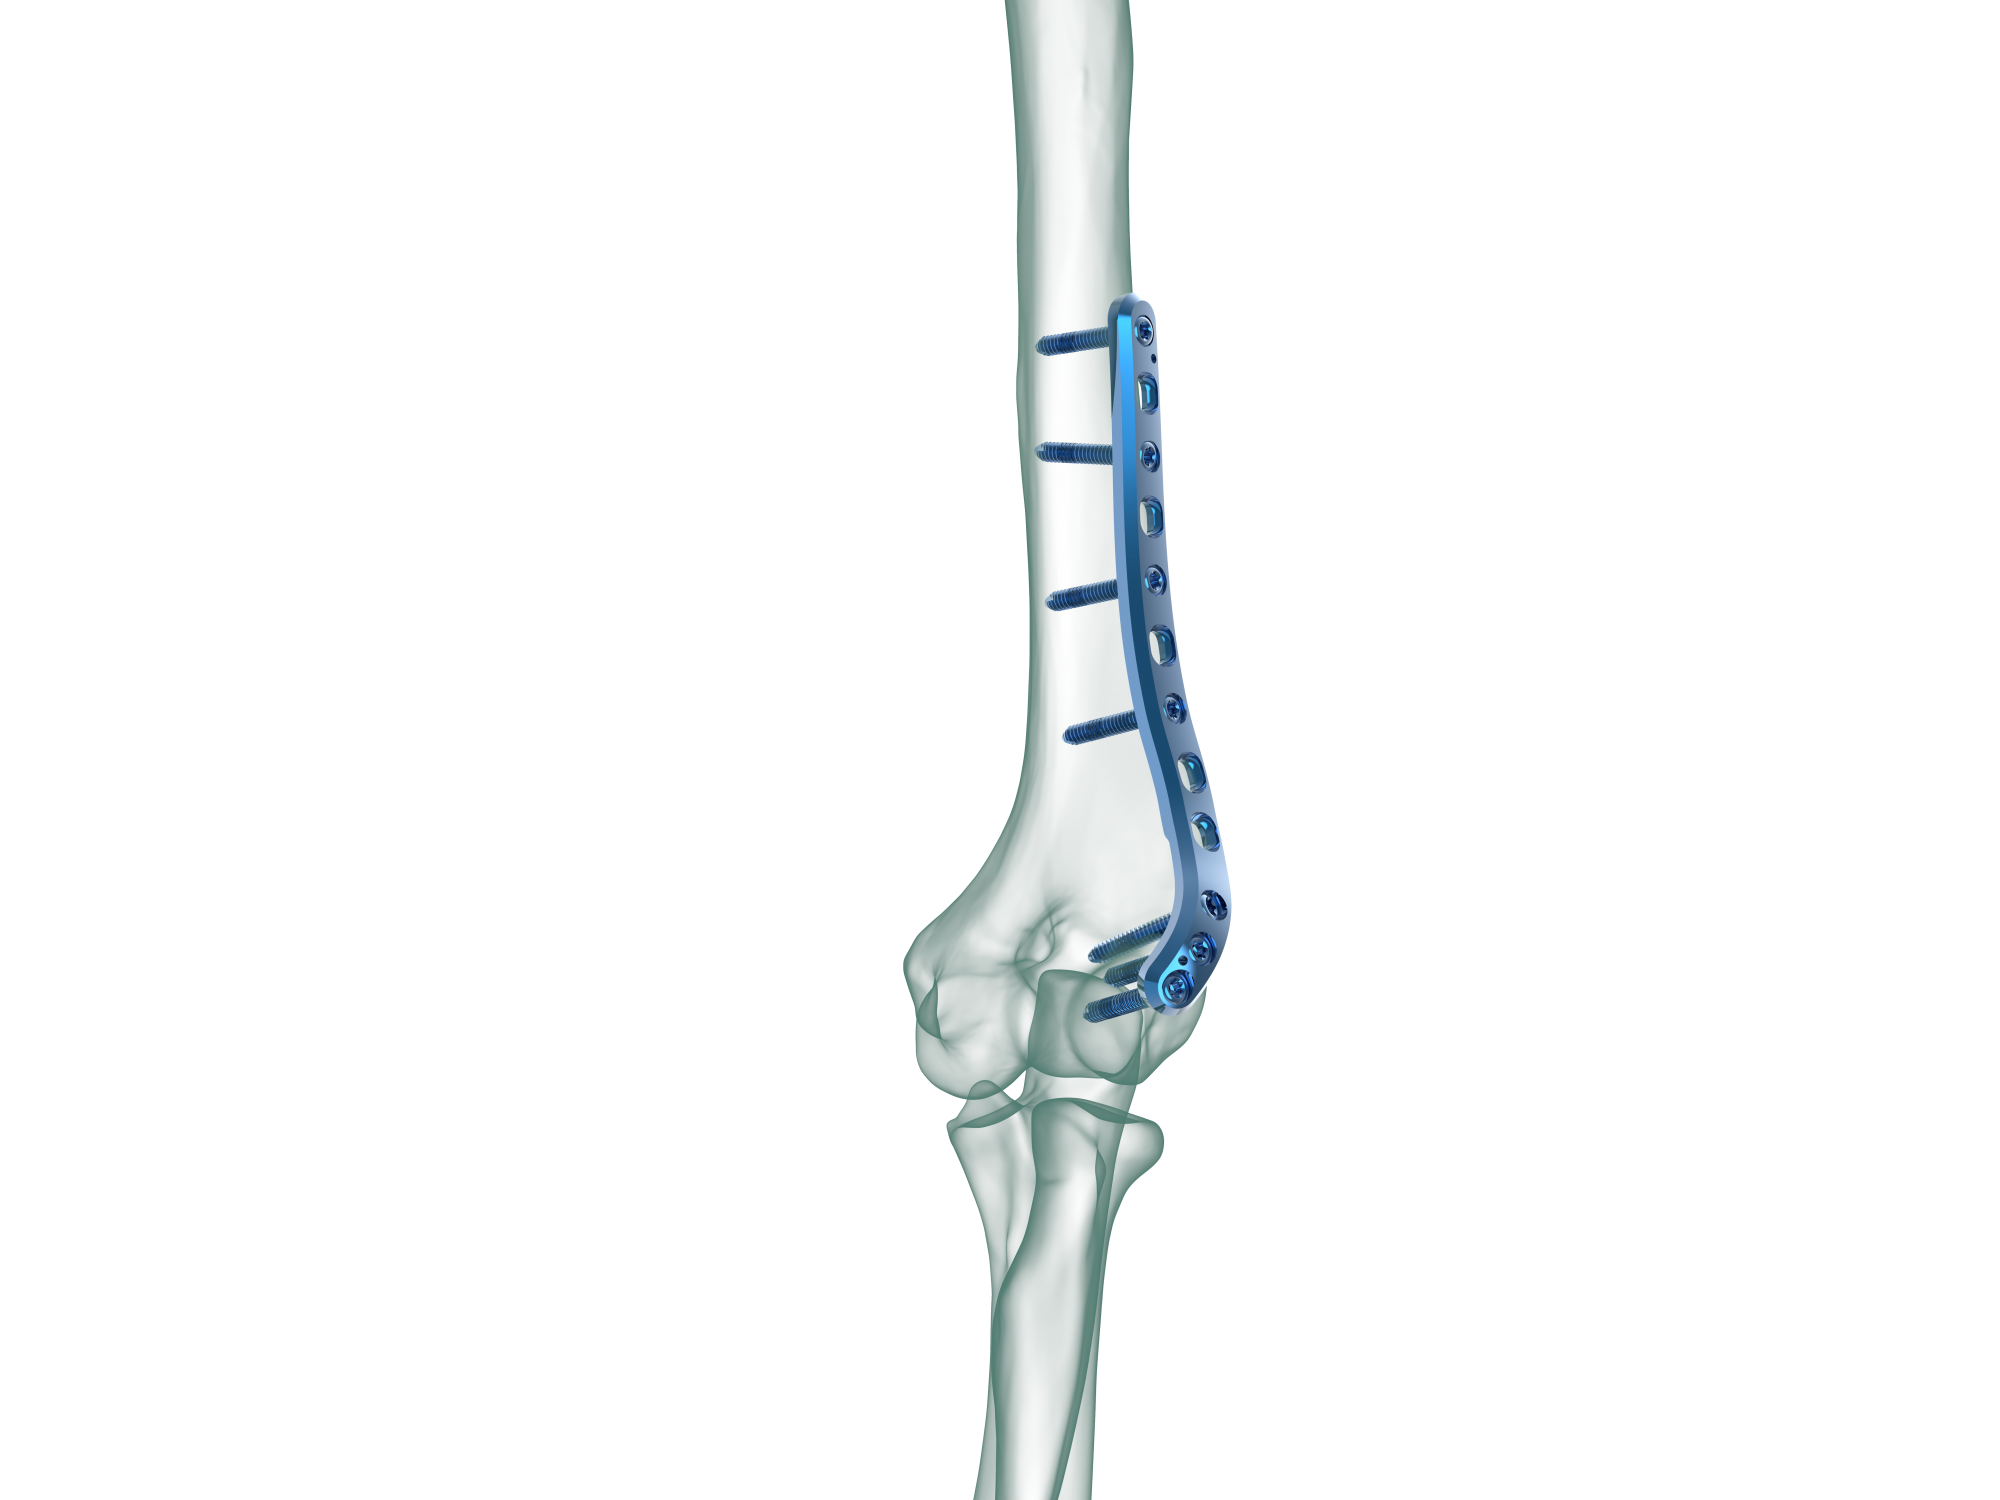

TRUE LOCK Distal Humerus Lateral Anatomic Plate

Anatomical plate; right & left

Low plate-and-screw profile and rounded plate edges minimize potential for tendon and soft tissue irritation.

TRUE LOCK Distal Humerus Lateral Anatomic Plates are precontoured for anatomic fit. No need to bend during the surgery.

Elongated Combi hole in the neck and shaft facilitate plate adjustment and allow locking or compression options.

The combi-hole pro- vides flexibility of axial compression and locking capability throughout the length of the plate shaft.